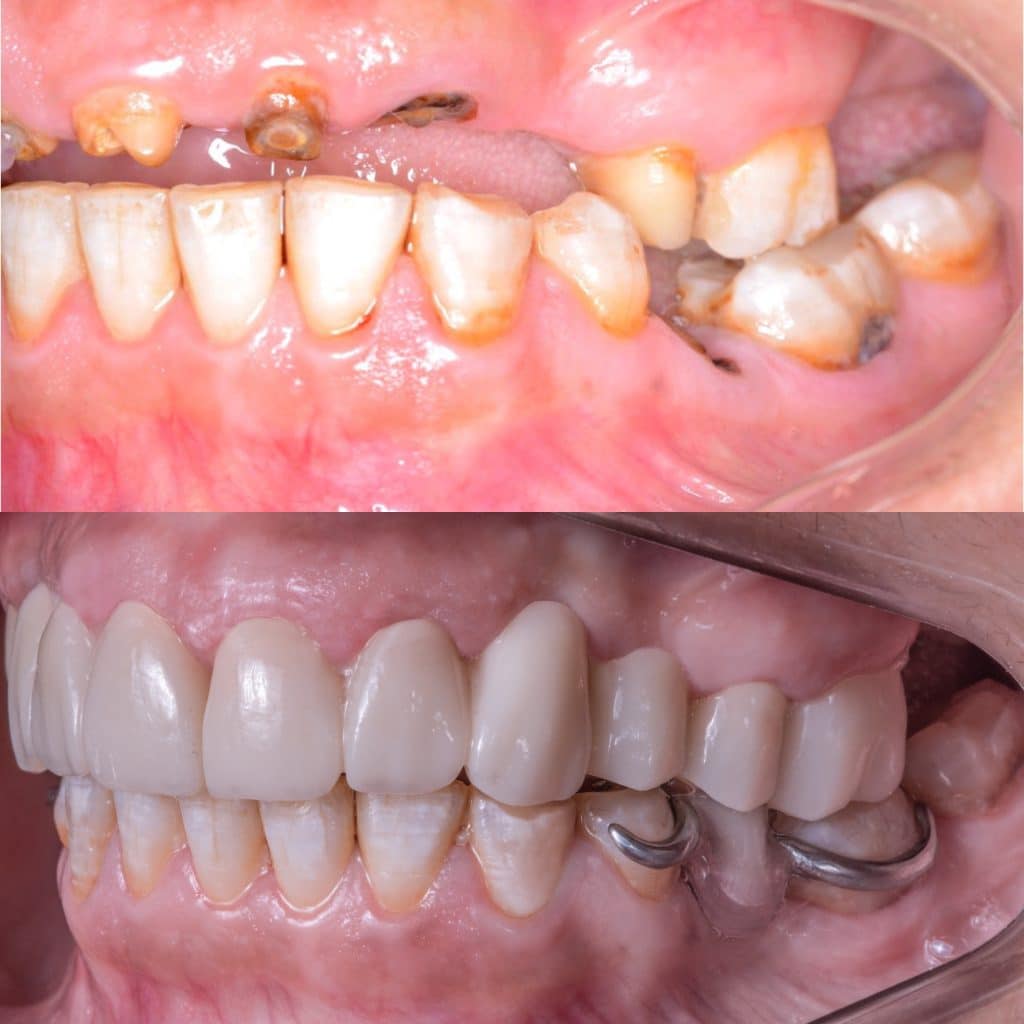

Full mouth rehabilitation case by 5th grade Dental student

42 years old female patient came to Pharos university in Alexandria egypt suffering from badly destructed teeth seeking her teeth to be restored

She lost her self confidencedue after losing her FPD for more than 2 years and she couldn’t smile or even eat !

The remaining tooth structure were broken with its old fiber posts due to malocclusion

- Preparation of two bridges from 4 to 8 & 9 to 14 with Horizontal prep and subgingival chamfer finish lineNote missing teeth are 6,11,12

- After cementation of the bridges, rest seats were prepared for the RPD

- Metalic Rpd fabricated for class 2 mod 1 kindey classification